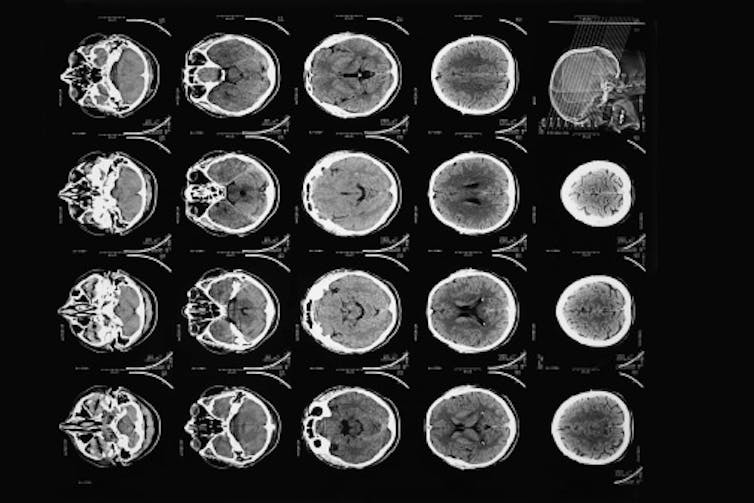

In 1973, American Robert Ledley developed a whole-body scanner that could image other organs, blood vessels and, of course, bones. Modern scanners are faster, provide better resolution, and most important, do it with less radiation exposure. There are even mobile scanners.

By 2020, technicians were performing more than 80 million scans annually in the U.S.. Some physicians argue that number is excessive and maybe a third are unnecessary. While that may be true, the CT scan has benefited the health of many patients around the world, helping identify tumors and determine if surgery is needed. They’re particularly useful for a quick search for internal injuries after accidents in the ER.